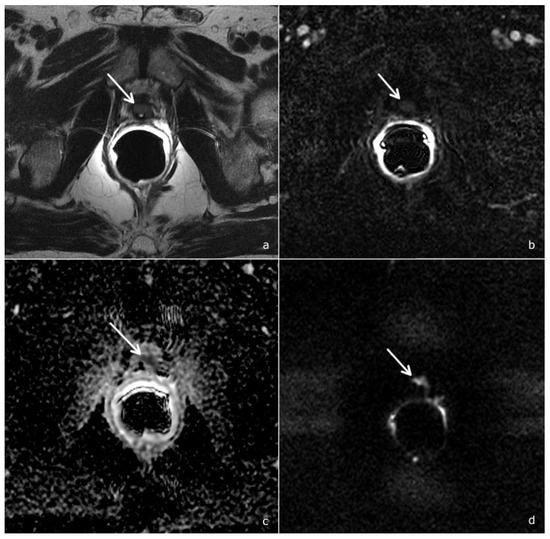

2.2. mpMRI Protocol Study

- Morphological study: Fast Relaxation Fast Spin Echo T2-weighted (T2w) sequences in the sagittal, axial and coronal planes, covering the prostate lodge.

- Diffusion-weighted imaging (DWI): a single-shot echo-planar sequence with a high b-value (2000 s/mm2) and another single-shot echo-planar sequence with two different b-values (50 and 1000 s/mm2), this latter for the calculation of the apparent diffusion coefficient (ADC) map.

- DCE acquisition: three-dimensional (3D) T1-weighted Time-of-Flight Spoiled Gradient-Recalled sequence on the axial plane during the intravenous injection of a gadolinium-based contrast agent at a flow rate of 3 mL/sec followed by 15 mL of saline solution. The 3D data sets were acquired with a 10 s temporal resolution; the acquisitions before the contrast agent administration were analyzed to detect foci of hemorrhage.

2.3. Image Analysis

- Scores of 1 and 2 were assigned to lesions with a very low and low likelihood of recurrence

- Score 3 was assigned if the presence of recurrence was uncertain

- Scores 4 and 5 were assigned when the likelihood of recurrence was high and very high